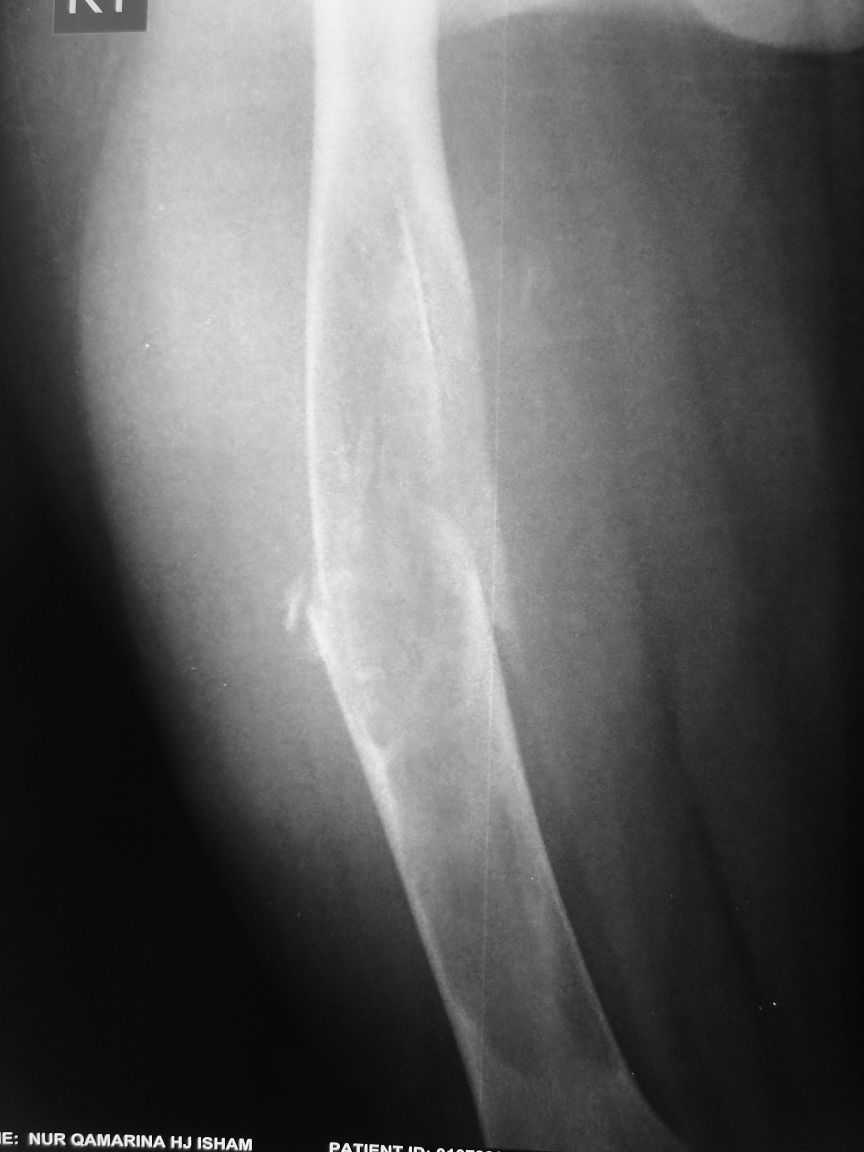

The attached xrays are of a 13 year old girl, who presented to us with a history of trivial trauma.

X-rays showed a pathological fracture right femur

through a large radioluscent expansile lesion. All

blood investigations are normal. Clinically no other positive findings. We assume this to be a case of fibrous dysplasia, and plan to do a biopsy from the site. Would like your opinion regarding any other possibility in the diagnosis and treatment options.